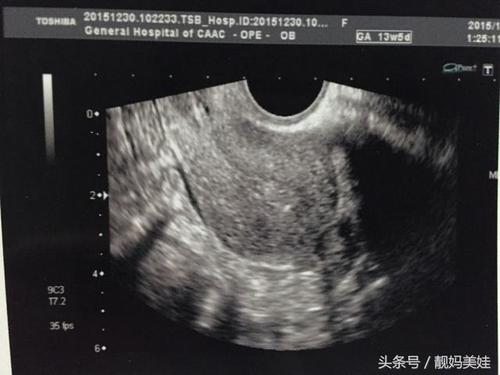

阴超是妇科内诊检查,是应用超声波的方式,不影响性状和排便。孕期做阴超,一般在停经40日,可以判断宫内孕还是宫外孕。

B超是妇科检查中的常规检查项目之一,它是检测宫内妊娠的方法之一。但是B超检查是有局限性的,如果发育情况和个体差异均能及早的发现,并且及时的采取有效的治疗,是不会影响下次的再次孕期的。